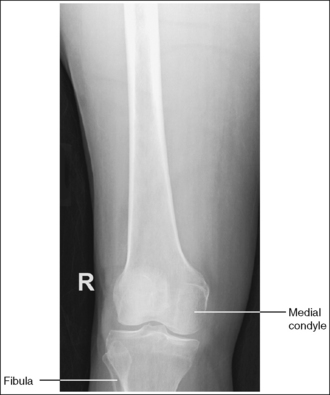

The lower leg demonstrates an AP projection. The tibia demonstrates only minimal superimposition of the proximal and distal fibula, and the fibular midshaft is demonstrated free of tibial superimposition.

Image density is uniform across the lower leg.

The tibial midshaft is at the center of the exposure field. The tibia, fibula, ankle, knee, and surrounding lower leg soft tissue are included within the collimated field.